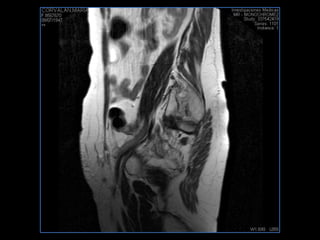

PROTOCOLO abdomen COR T2, AXIAL supresion grasa AX T1 +SAG T2  CON   GADOLINIO :  COR T1+AX T1(DIN) SAT: NO  FASE: RL THK: 6MM  COIL:  GAP: (FACTOR 1.4) 2MM FOV: 40 CM NEX:2 SINCRONIZACION RESPIRATORIA EN 3 O 4 CICLOS ALE

PROTOCOLO pelvis SAG T2, Y FAT SAT (FINOS) AXIAL T1  AX FAT SAT CON   GADOLINIO :  AX T1 Y COR T1 SAT: NO  FASE: RL THK: 3MM  COIL:  GAP: (FACTOR 1.4) 1MM FOV: 40 CM NEX:2 SINCRONIZACION RESPIRATORIA EN 3 O 4 CICLOS ALE